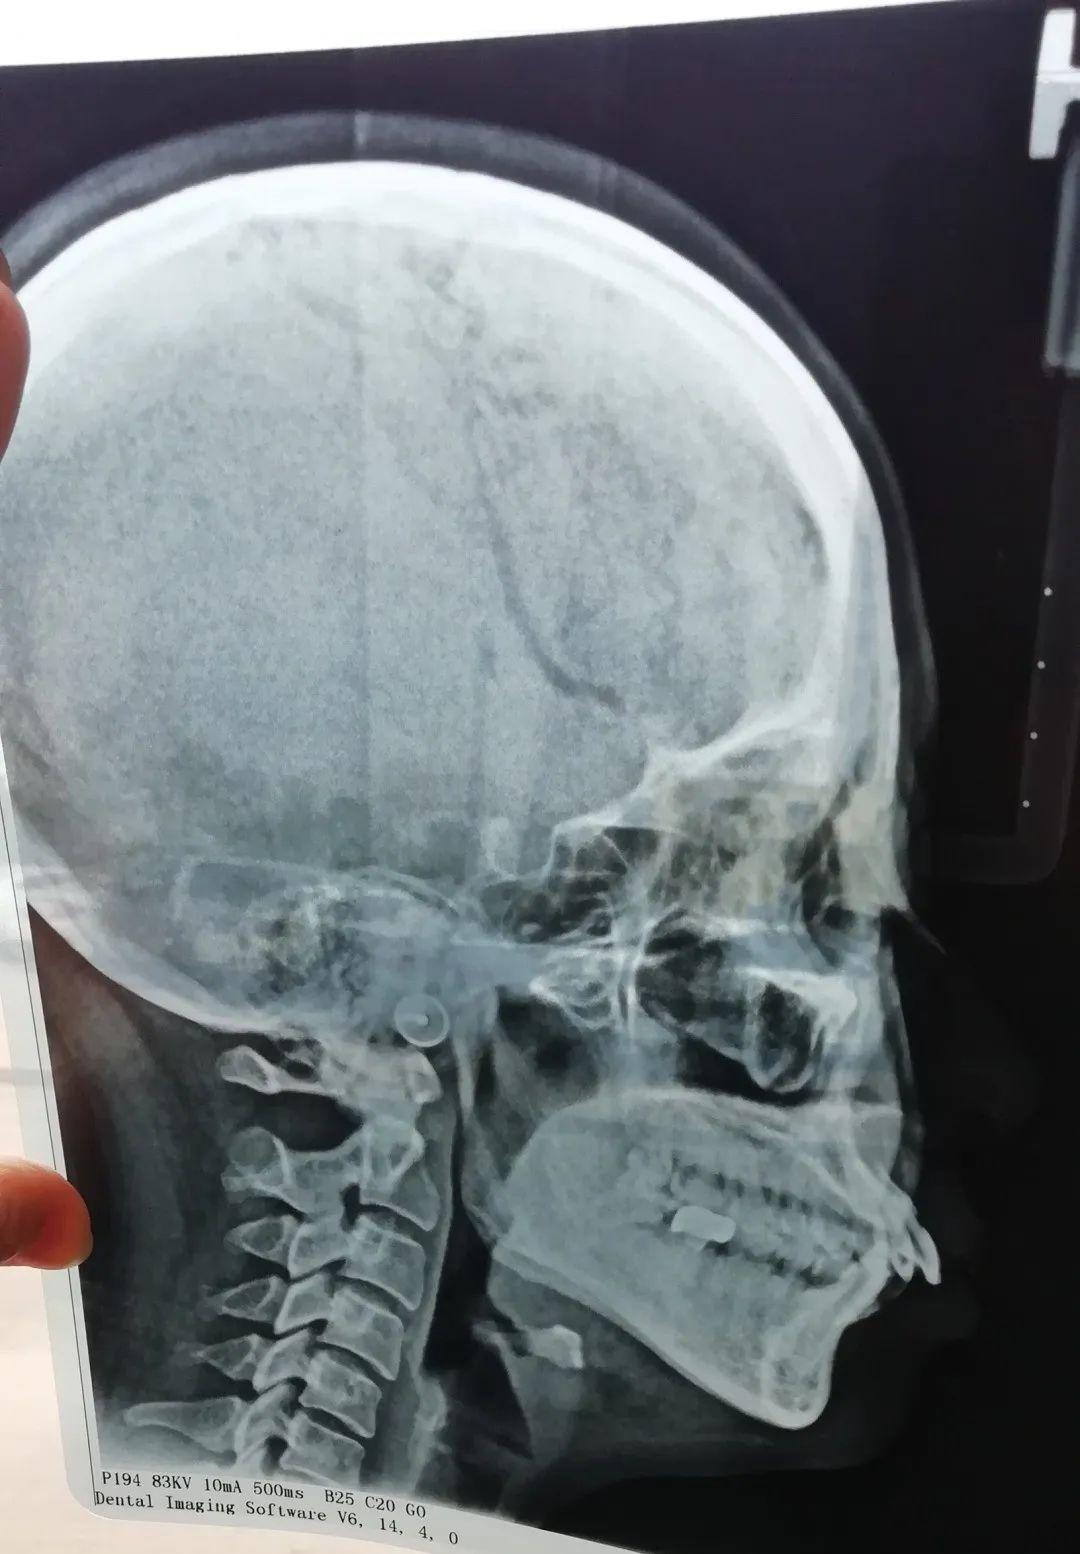

比如ct片、牙片,可以清晰的看出牙齿的问题

我拍出的片子……真是一言难尽

我不惜献丑让大家看我的牙片,正面看主要是中间牙齿的排列不齐,但从侧面看简直惊人,以前觉得我的凸嘴可能就是骨性问题,也不觉得上牙齿有多难看,看牙片就会发现这龅牙龅的也太离谱,不整都对不起自己。